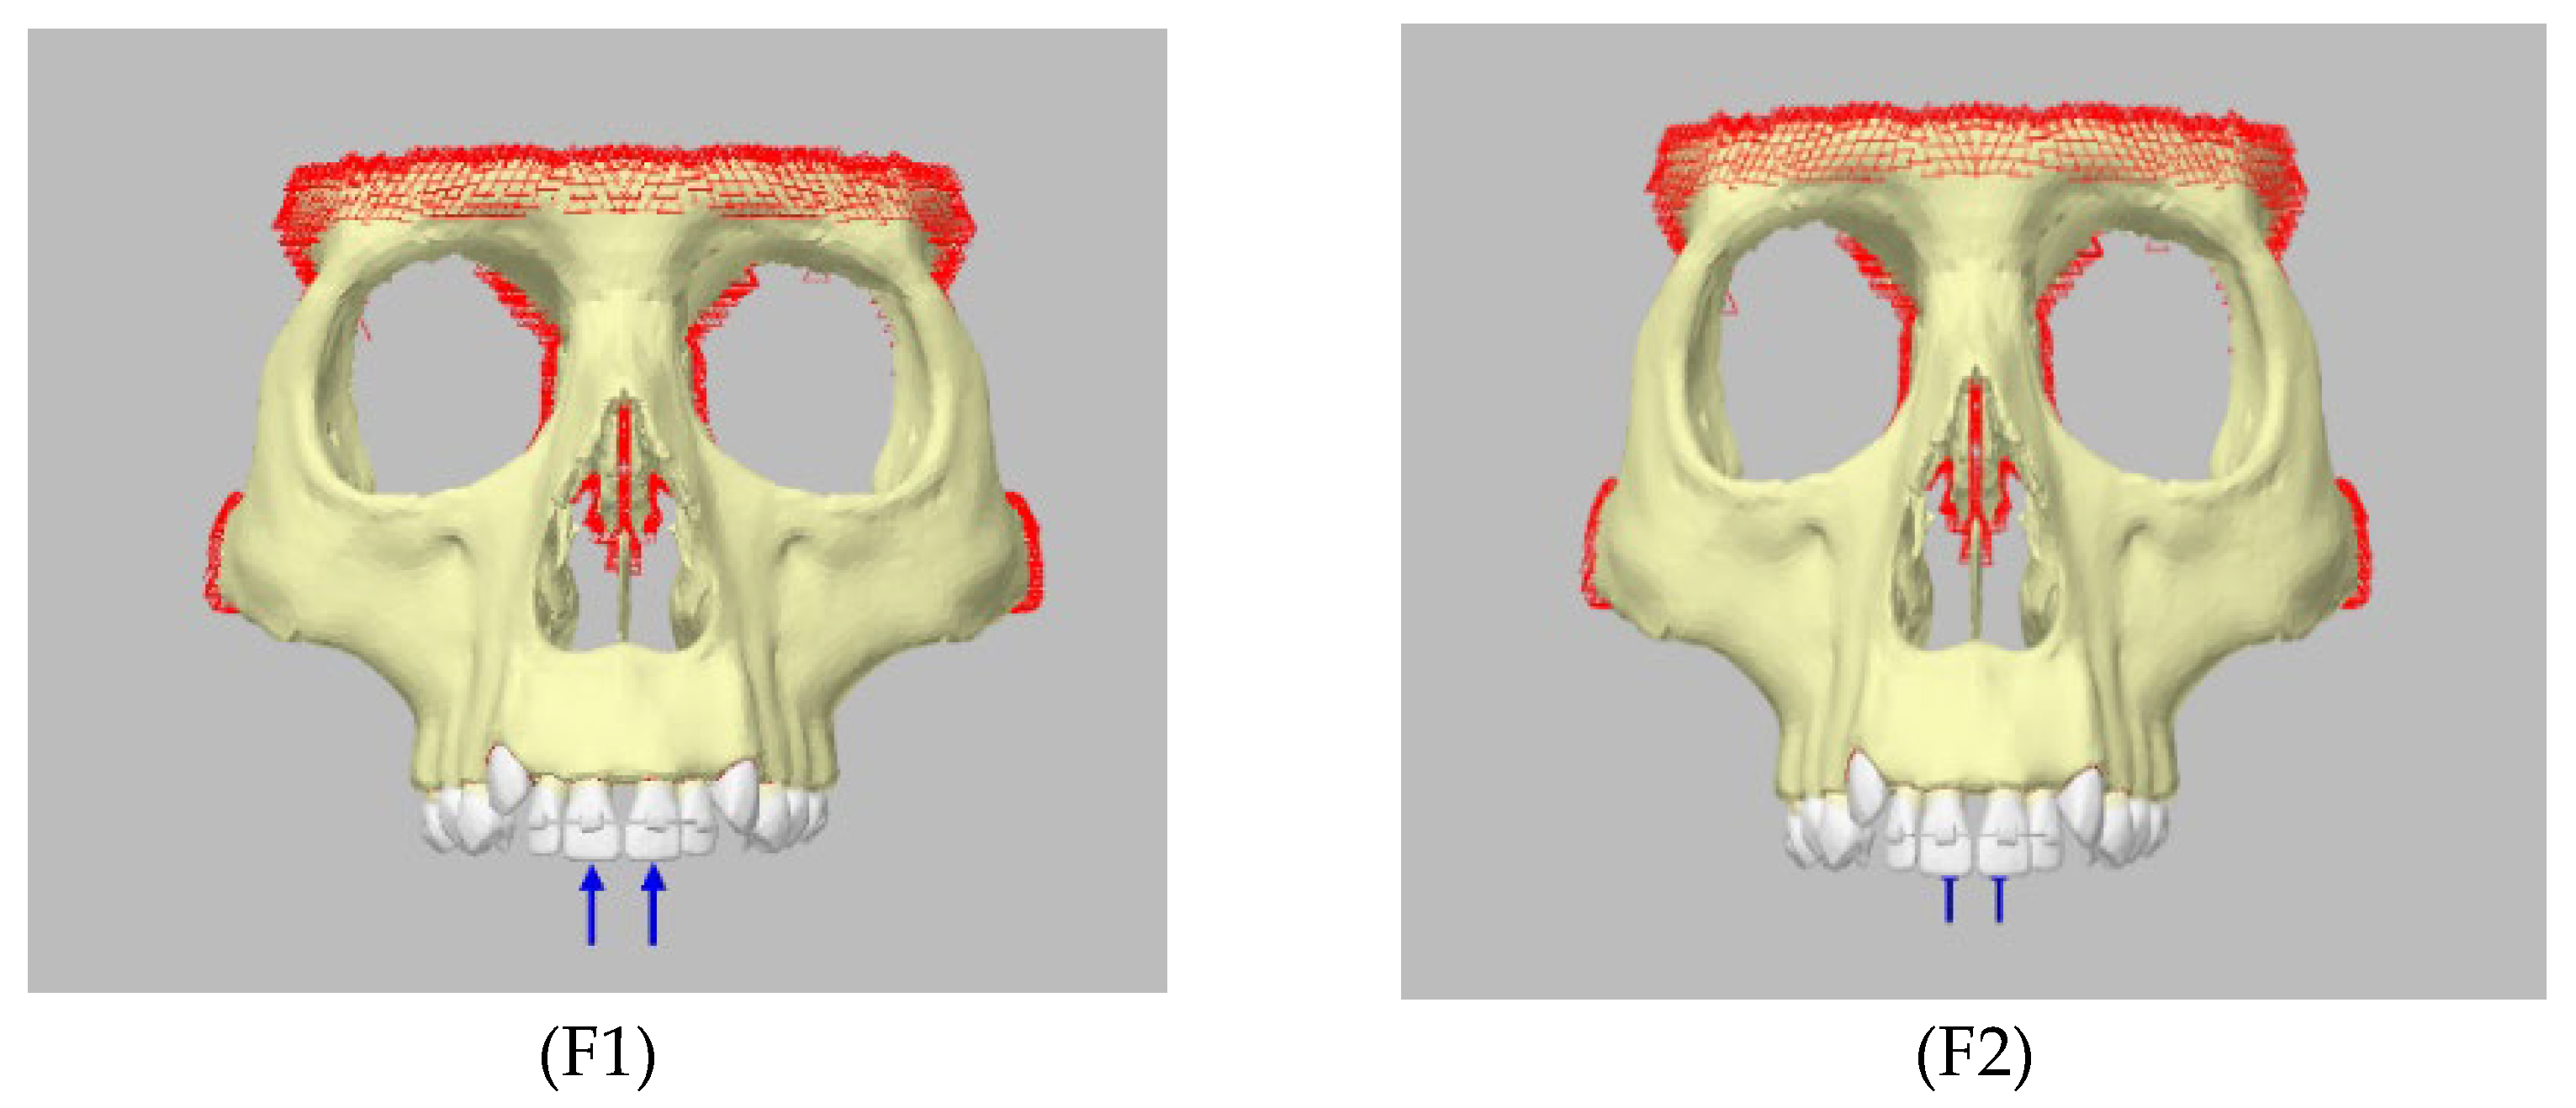

2. Materials and Methods